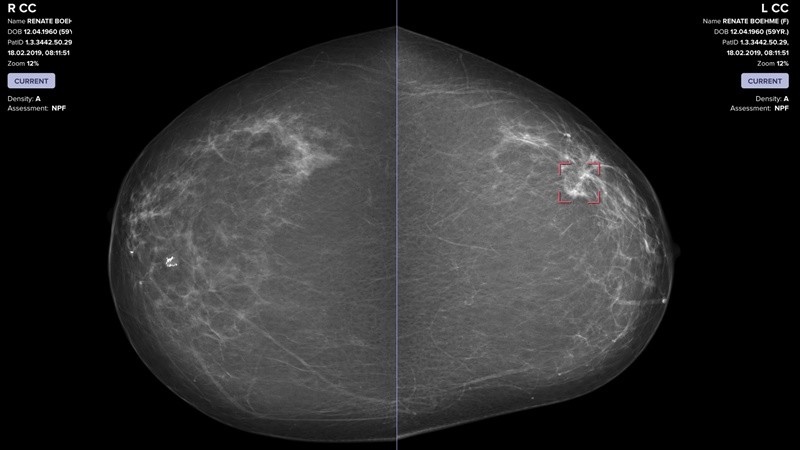

Un ejemplo concreto de este antes y después en la historia de la salud se encuentra en la detección del cáncer de mama. Aquí, los algoritmos de aprendizaje automático demostraron una rigurosidad extraordinaria para identificar señales microscópicas que indican un comportamiento celular anormal. Un estudio realizado en Suecia entre casi 106.000 mujeres de entre 40 y 74 años reveló que el screening asistido por IA detectó un 29% más de casos de cáncer de mama en comparación al método convencional de doble lectura por radiólogos. Además, este aumento en la detección incluyó un 24% más de tumores invasivos en etapa temprana y un 51% más de lesiones precancerosas, factores decisivos para mejorar el pronóstico y evitar tratamientos más agresivos.